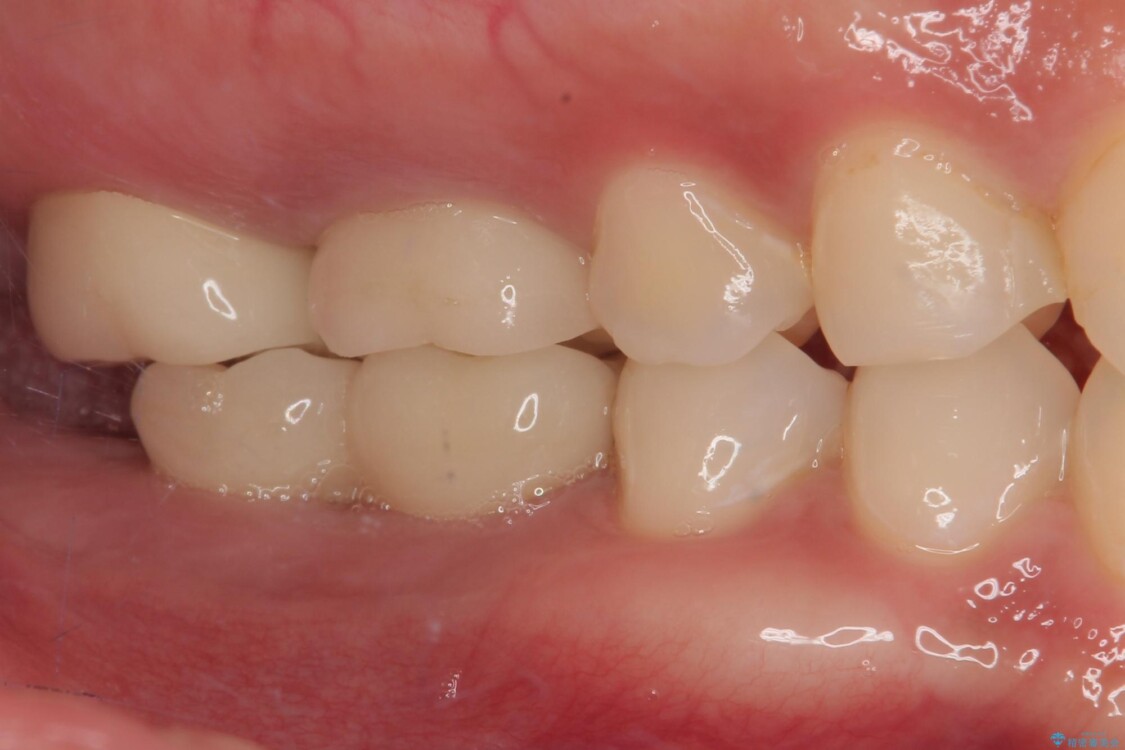

スペースが整った段階で、右下の第一大臼歯と第二大臼歯にインプラントを埋入。

その後、挺出していた右上第一大臼歯と第二大臼歯に装着されていた銀歯についても、審美性と適合性の向上を目的に、オールセラミッククラウンにやり替えました。

これにより、より自然で美しい見た目と、高い精度の咬合が得られています。

治療後

• 挺出歯を圧下してスペースを確保!目立たない部分矯正で下顎大臼歯にインプラント治療を実現 治療後画像